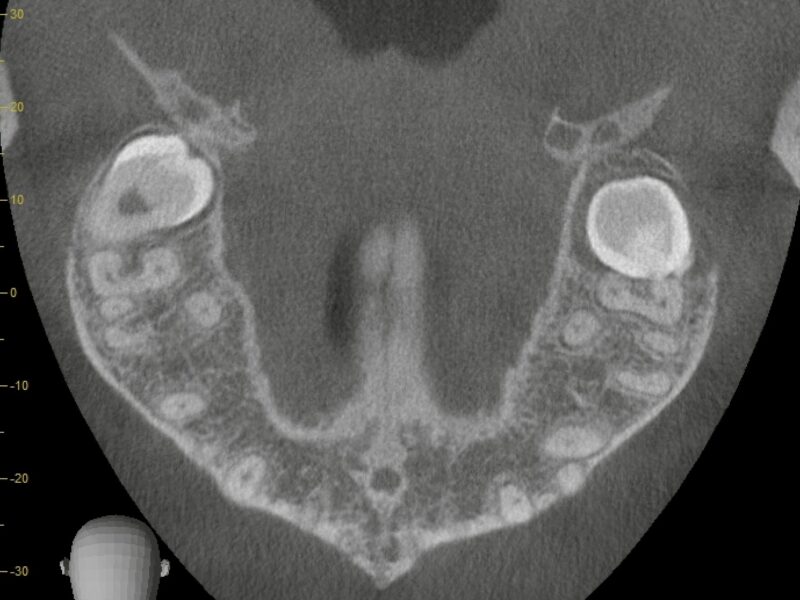

特徴4高精度診断を可能にする「歯科用CT」 -